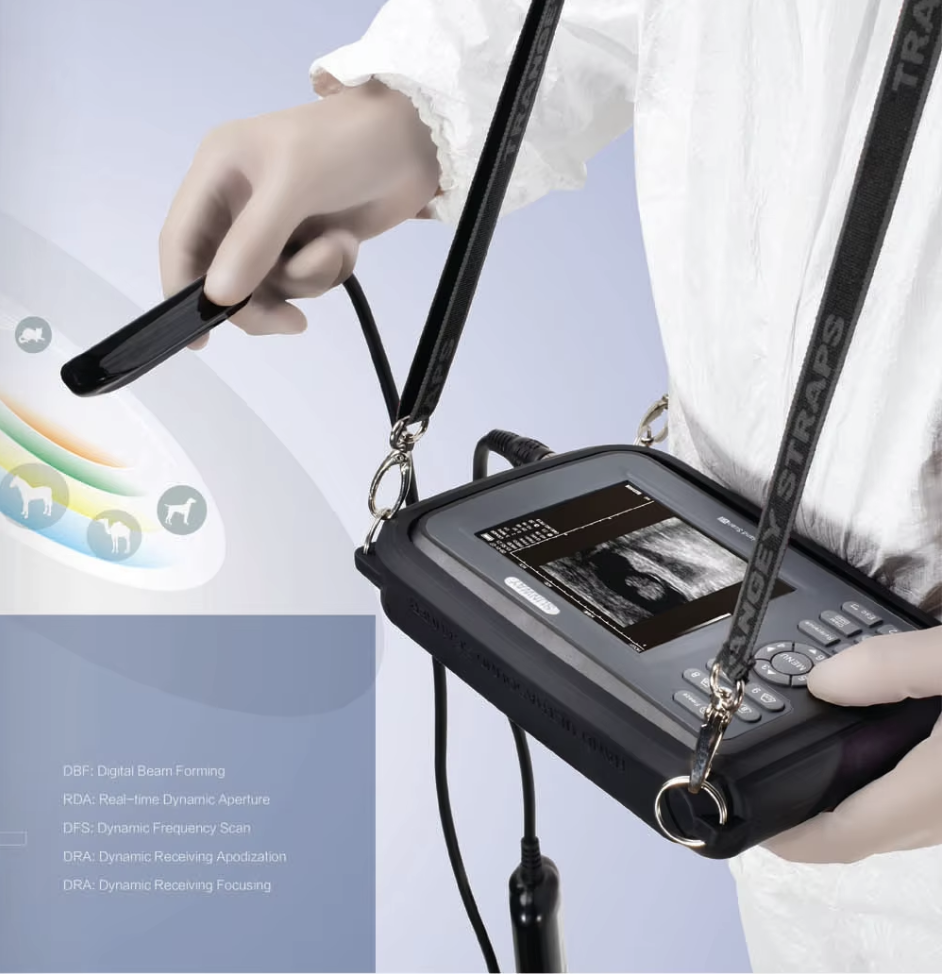

- V8 es un escáner de ultrasonido pequeño, compacto y alimentado por baterías para aplicaciones veterinarias en cualquier parte del campo

- Diseño ergonómico para sentarse cómodamente

- Resistente a salpicaduras y resistente al polvo.

- Funciona con pilas

- Peso ligero

- Tamaño de la pantalla: 5,5 pulgadas, LCD en color TFT